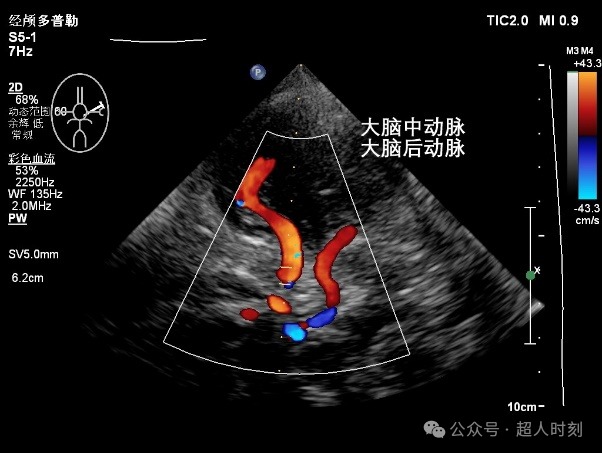

为了更进一步地探测脑血管的情况,经颅彩色多普勒血流成像(transcranial color coded Doppler,TCCD)也在临床得到了广泛应用。2016年发布的《中国脑血管超声临床应用指南》就介绍并推荐了TCCD的使用,且对TCD和TCCD做了比较说明(图1);总之,就是TCCD更加直观、准确,也能给医生提供更多的信息。

图1

TCCD(图3)不仅能够得到TCD那样的频谱图,还能直观看到血管的走行和血流的状态,是可视化医学的一个明显特征。

图3a

图3b

图3c